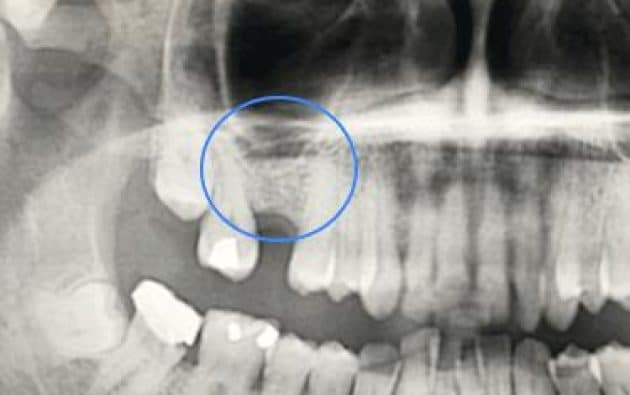

Antes y después de una elevación de seno maxilar

En estas imágenes puedes ver el antes y después de una elevación de seno maxilar realizada en nuestra clínica.

En la primera radiografía se observa la falta de hueso en la zona posterior del maxilar superior. En la segunda imagen, ya regenerada, se aprecia el implante dental correctamente integrado.